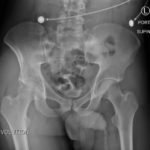

The initial radiograph of the pelvis revealed bilateral hip dislocations. Small bony fragments were noted in the right hip joint, suggestive of an underlying fracture. The sacroiliac joints and the pelvic ring were intact. In the emergency department, bilateral hip reductions were performed using the Captain Morgan technique.1 The post-reduction film showed reduction of the bilateral hip dislocations with extensive comminuted and displaced fractures of the right and left acetabula.